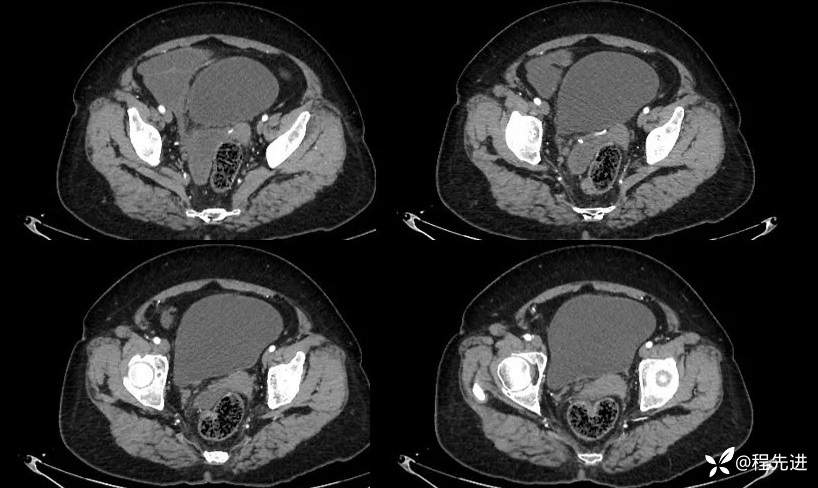

平扫:

动脉期: